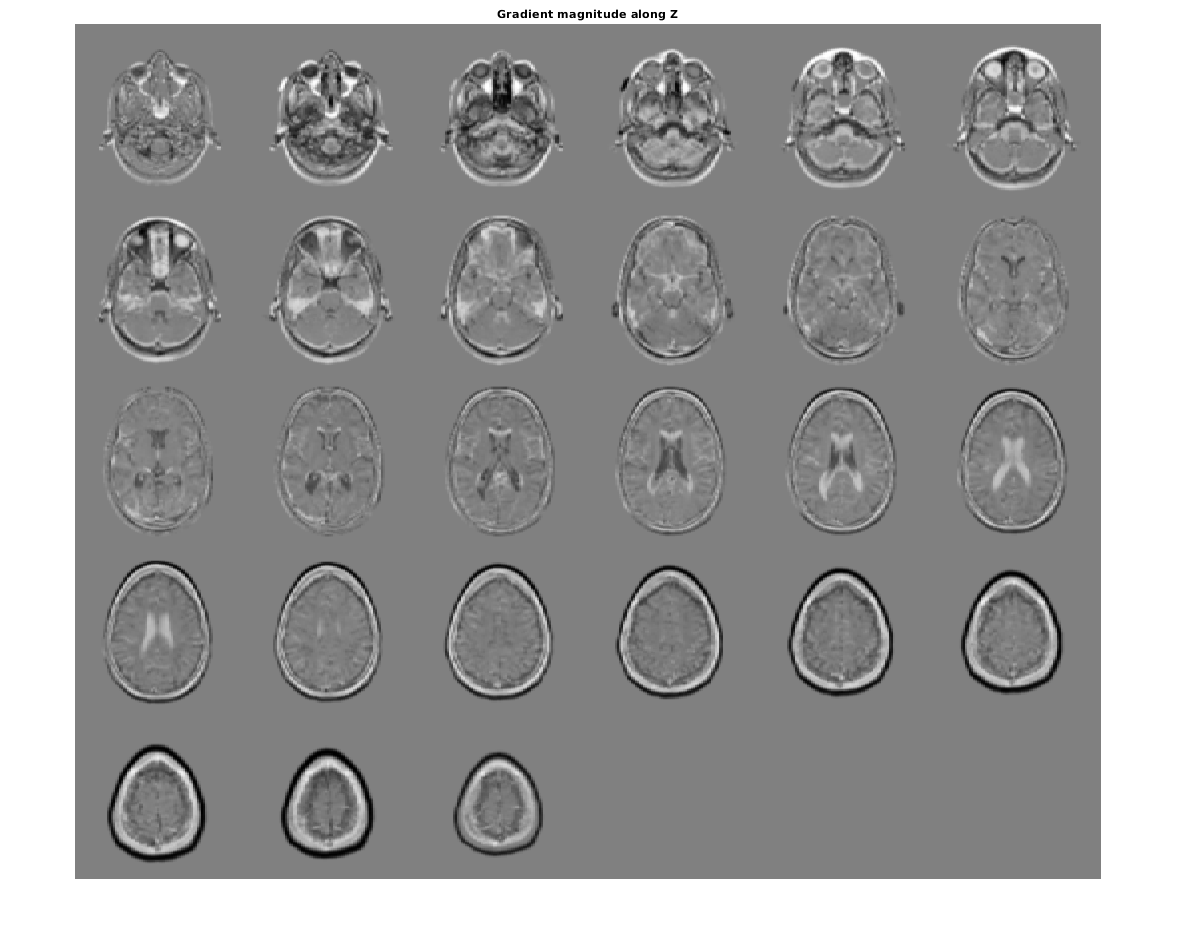

figure, montage(reshape(Gz,sz(1),sz(2),1,sz(3)),'DisplayRange',[])

title('Gradient magnitude along Z')

Figure contains an axes object. The axes object with title Gradient magnitude along Z contains an object of type image.